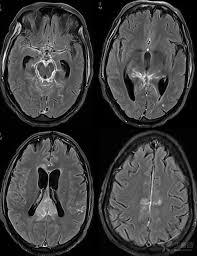

5.CT,MRI檢查,腦CT約半數顯示異常,炎性滲出物充填基底池及腦外側裂,部分患者腦實質內顯示結核瘤,直徑0.5~5cm,單發或多發,多位於額,顳及頂葉,增強掃描顯示環狀強化或密度增高。

腦MR採用Gd-DTPA增強,顯示基底池等部位強化,並較易發現腦實質內的結核瘤和小梗死灶。